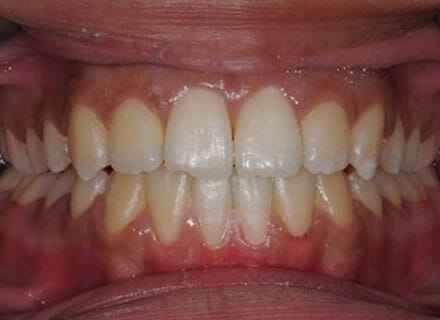

This patient came to us because she hated her smile: it was too narrow, the upper front teeth were all crowded into each other and twisted. She couldn’t eat a sandwich properly with the front teeth because of the gap – the open bite. We were able to expand both jaws to make space to align all the teeth without having to extract – in about 18 months using clear brackets.